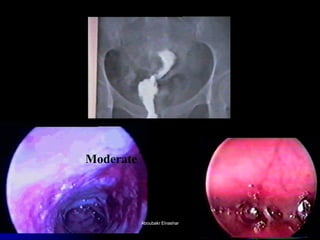

The document discusses the history and development of hysteroscopy. It began in 1869 but did not achieve routine use until improvements to optics, distension media, lighting and instruments in the 1970s-1990s allowed for office procedures without anesthesia. Today, many hysteroscopic procedures have replaced older, more invasive techniques. The document then provides details on rigid and flexible hysteroscopes, lighting sources, distension media, and diagnostic and operative uses of hysteroscopy for conditions like abnormal bleeding, infertility, uterine anomalies and assisted conception. Contraindications are also outlined.